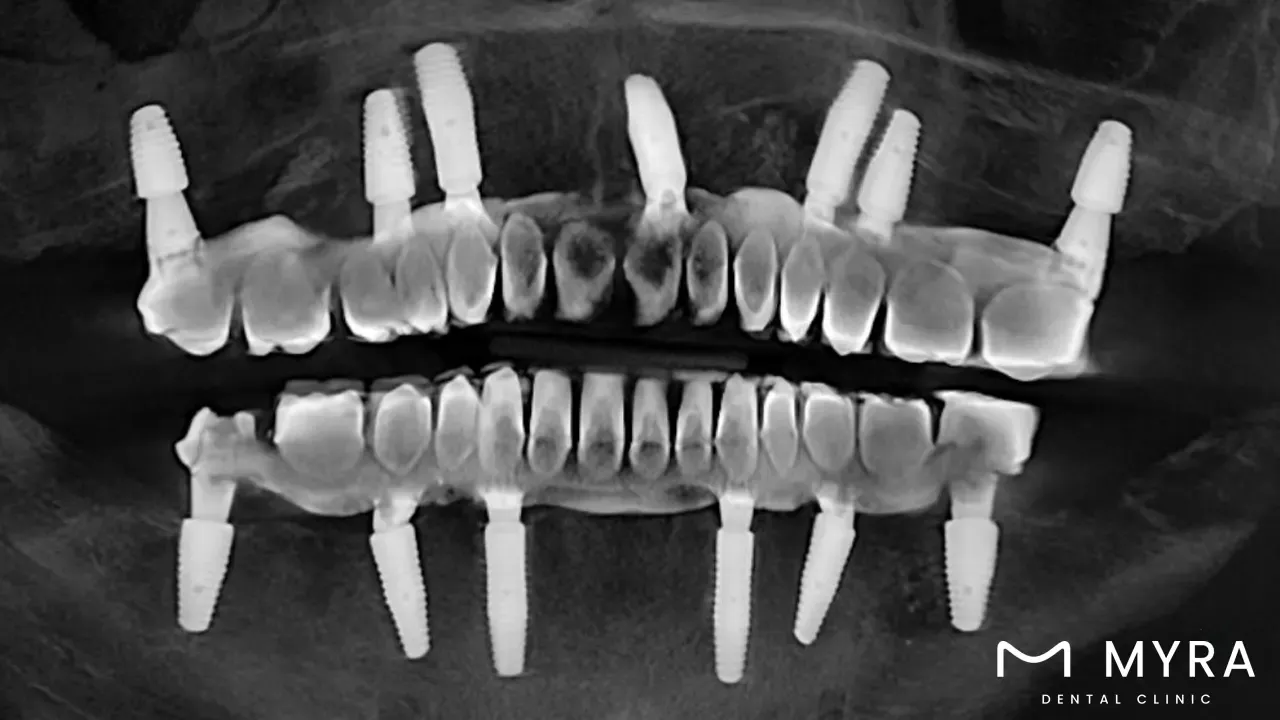

Dental implant surgery techniques involve various approaches to replacing missing teeth by surgically placing artificial tooth roots into the jawbone. The most commonly used technique is the Endosteal implant, which is inserted directly into the bone and offers high success rates and long-term durability. For patients with insufficient bone height or density, techniques such as Subperiosteal implants, Bone Augmentation, Sinus Lift, and Ridge Expansion are applied to strengthen or build up the jawbone before implant placement.

Other advanced options include Mini Dental Implants (MDIs), ideal for patients with limited bone or space, and Immediate Load Dental Implants (Same-Day Implants), which allow for quicker restoration and immediate tooth function. The All-on-4® technique replaces a full arch of teeth using only four implants, offering a stable, aesthetic solution for those missing multiple teeth.

Dental implant surgery is a type of oral surgery that comprises replacement of a missing tooth with a prosthetic tooth root, which is commonly composed of titanium. Dental implants are put into the jawbone via surgery, and then given time to integrate with the bone naturally. A crown is able to be placed to it using an abutment to serve as a substitute tooth once the implant has bonded with the bone.

The process of getting dental implants normally entails a number of steps, one of which is having a consultation with a dentist or oral surgeon to establish whether or not the individual is a good candidate for the treatment. Imaging techniques like X-rays are used to determine the state of the jawbone and the positioning of any nearby teeth.